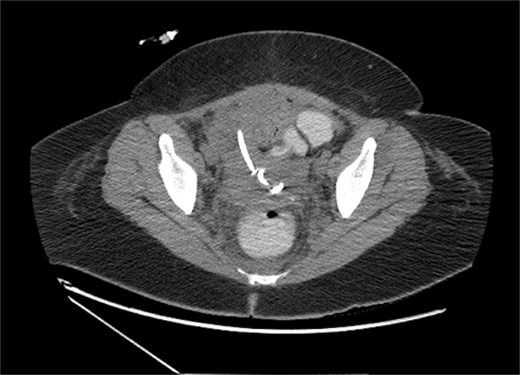

Over the next week, the catheter drainage volume gradually decreased and became minimal. Interval imaging was obtained and revealed minimal decrease in the size of the pelvic fluid collection to 10.7 × 7.7 cm. The 8.5 French drain was then upsized to 12-French (Fig. 3), with withdrawal of only 3 cc seropurulent output upon exchange. The next day, the drain output remained minimal at 15 cc, and the patient remained persistently tachycardic in the 130 s. At this point, the patient’s hospital course was not only complicated by pulmonary embolism, but also bilateral pleural effusions that had been increasing in size and rhabdomyolysis secondary to daptomycin. Due to the acute risk of acute kidney injury (AKI) from rhabdomyolysis, daptomycin was discontinued, and the patient’s antibiotic regimen was adjusted to ceftriaxone and flagyl.

Pelvic fluid collection on upsizing IR drain from 8.5 to 12 Fr, measuring 10.7 × 7.7 cm prior to tPA-dornase instillation, in the axial view.